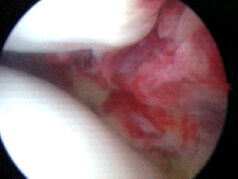

Schleimhautveränderungen:

Bei entzündeter Schleimhaut mit Flüssigkeitsbildung im Gelenk kann die Entfernung/Teilentfernung dieser indiziert sein (mit anschließender histologischer Untersuchung zur Ursachenklärung). Ebenso können verdickte Schleimhautfalten Schnappgeräusche im Gelenk auslösen und Schmerzen verursachen (häufigste verdickte Schleimhautfalte: "Plica mediopatellaris").